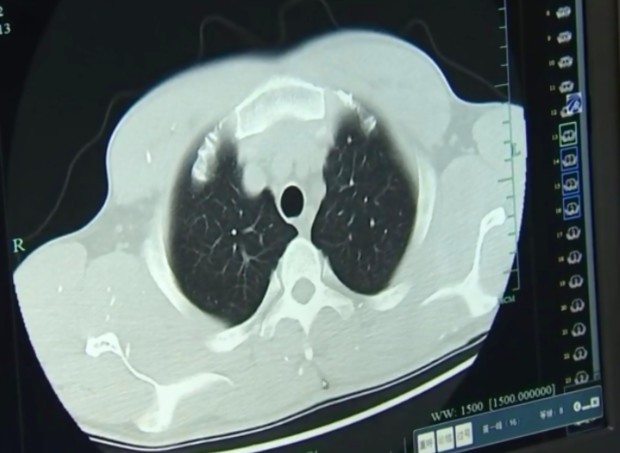

Como o cérebro humano é muito vascularizado, os animais costumam se instalar por lá. Ainda assim, outras regiões também estão em risco: o próprio Zhu apresentou infestação nos pulmões.